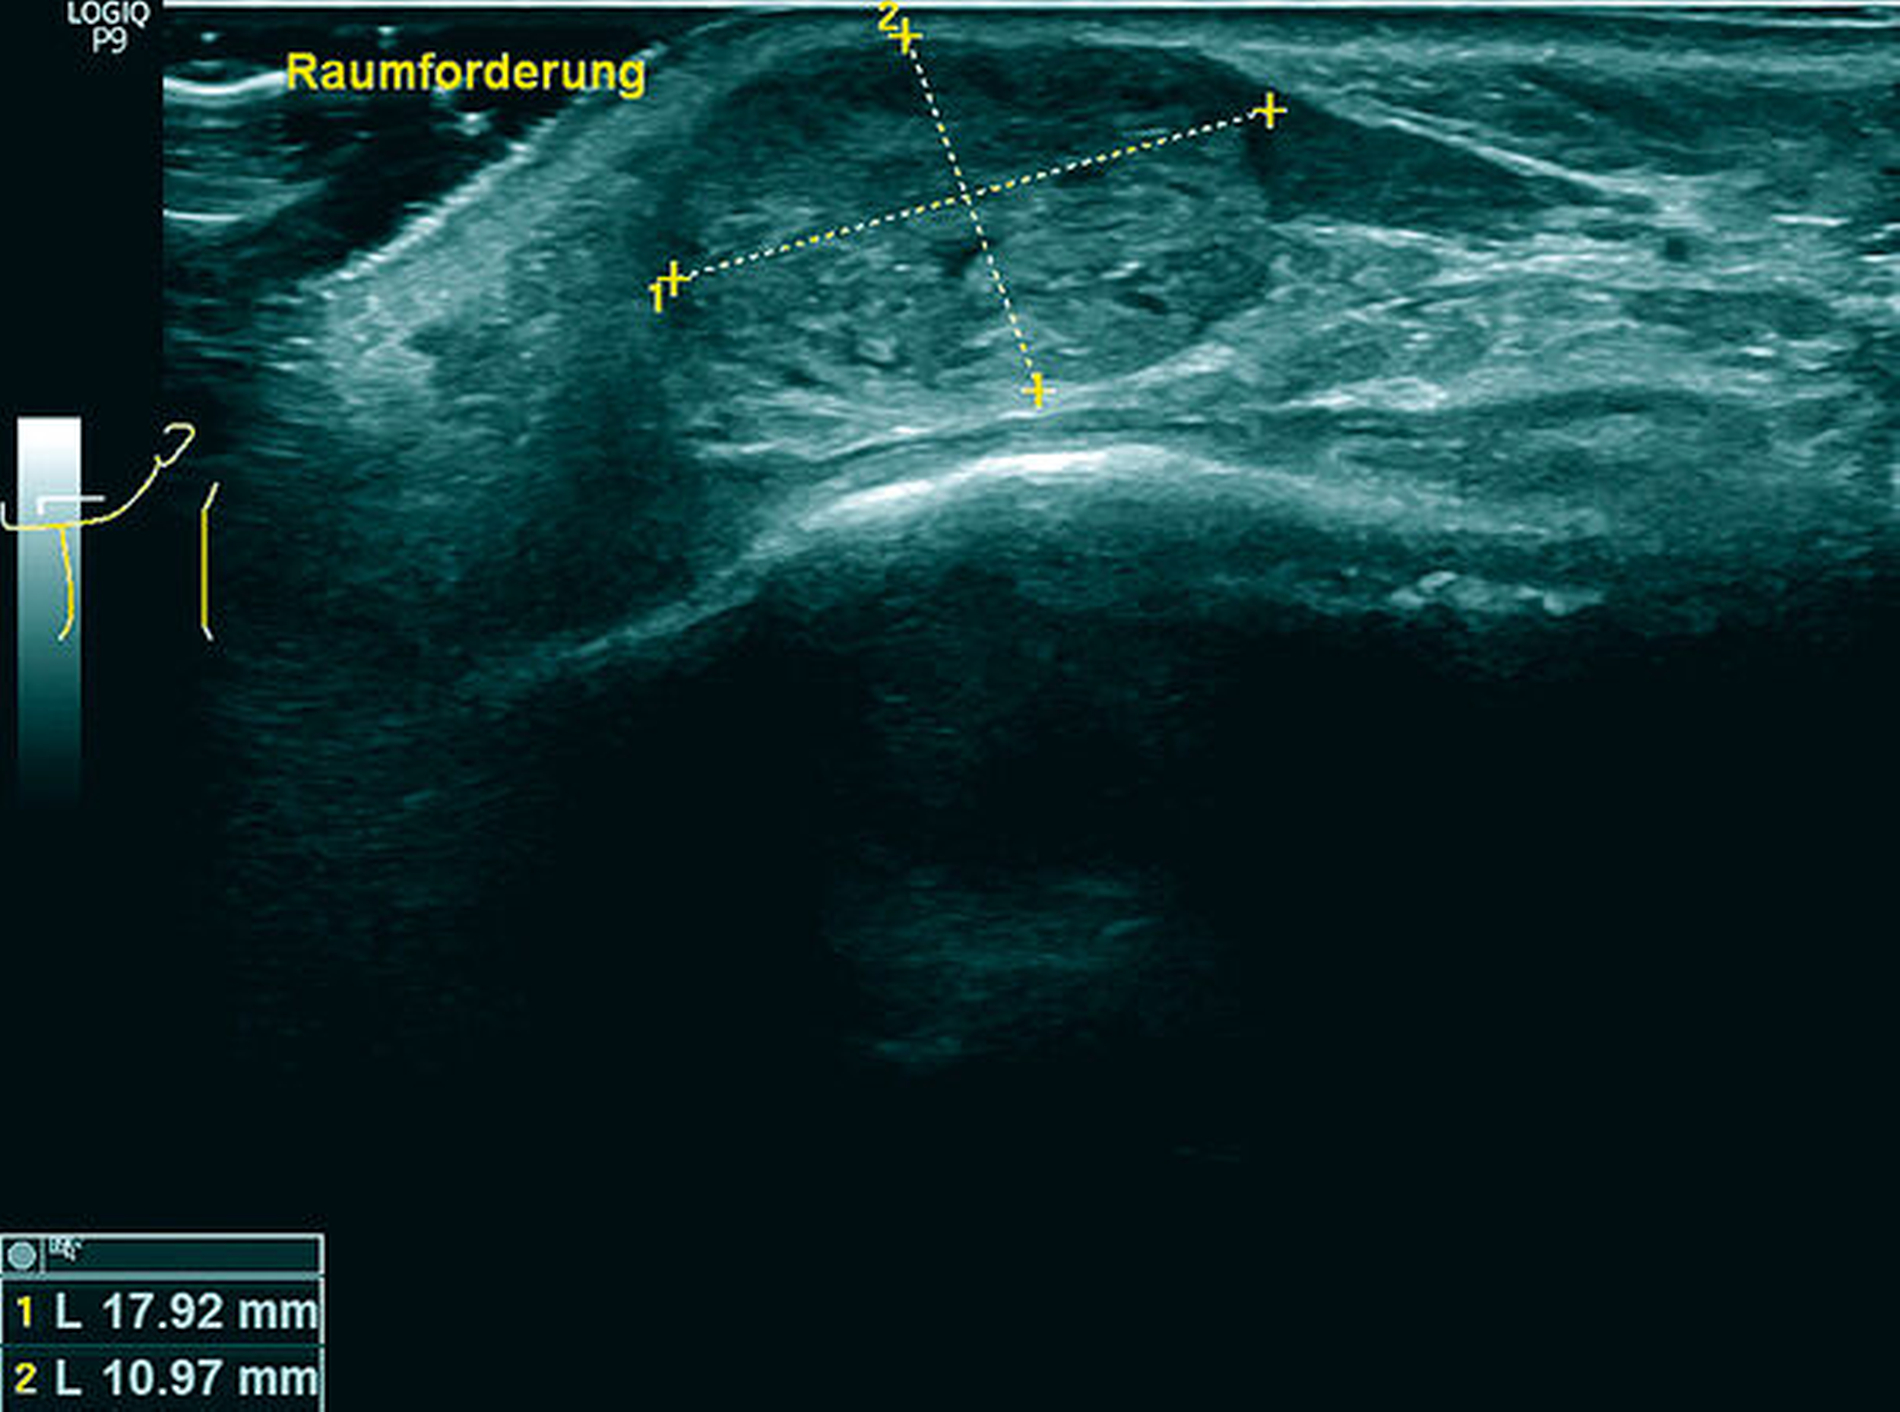

Eine am selben Tag durchgeführte sonografische Untersuchung des klinischen Befunds ergab eine ovaläre, homogen-echoreiche Schallantwort mit scharfer Begrenzung (Abbildung 2). Im zusätzlich durchgeführten Orthopantomogramm bildete sich die Raumforderung nicht ab.

Zunächst lag im oben beschriebenen Patientenfall mit einer Raumforderung an der Unterlippe linksseitig und dem aufgebotenen klinischen Bild sowie dem anamnestisch angegebenen Trauma (Abbildung 1) die Verdachtsdiagnose eines infizierten Hämatoms mit Abszessbildung nahe. Bei der Anamneseerhebung mit dem langwierigen Verlauf und dem angegebenen Trauma in der Vorgeschichte sollte differenzialdiagnostisch auch ein Fremdkörpergranulom oder eine spezifische Infektion in Betracht gezogen werden. Nach der weiteren sonografischen Diagnostik konnten diese in unserem Fall weder ausgeschlossen noch bewiesen werden. Der Vorteil der Sonografie lag hier in der schnellen Ausschlussmöglichkeit einer vaskularisierten Gefäßneubildung, einer Zyste oder eines Abszesses. Da sich bei fehlender dorsaler Schallverstärkung und nicht nachweisbarem Dopplerecho kein Hinweis auf einen flüssigkeitsgefüllten, epithelial ausgekleideten oder perfundierten Hohlraum zeigte (Abbildung 2), konnten diese Differenzialdiagnosen somit schnell ausgeschlossen werden. Weiter ist die Lokalisation der Unterlippe und der Wange für eine Pathologie der kleinen oder der großen Speicheldrüsen untypisch und macht auch hier die Diagnose unwahrscheinlich. Letztendlich war zur Diagnosesicherung die histografisch kontrollierte Exzisionsbiopsie indiziert, die im beschriebenen Fall eine metachrone Absiedlung eines klarzelligen NZK nachweisen konnte.